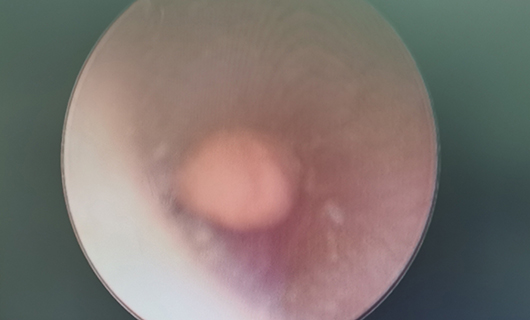

近日,6岁女孩桃桃(化名)因左耳内塞进一块橡皮泥来耳鼻喉科就诊。因为异物位置较深,一碰就疼,桃桃很难配合医生。医生决定做全麻下耳内镜异物取出术,经详细检查、鉴别诊断,启动了日间手术。桃桃就诊当天下午就住院了,手续办齐后,医生为其做了手术。次日早上,桃桃术后一切良好,高高兴兴地出院上学去了。